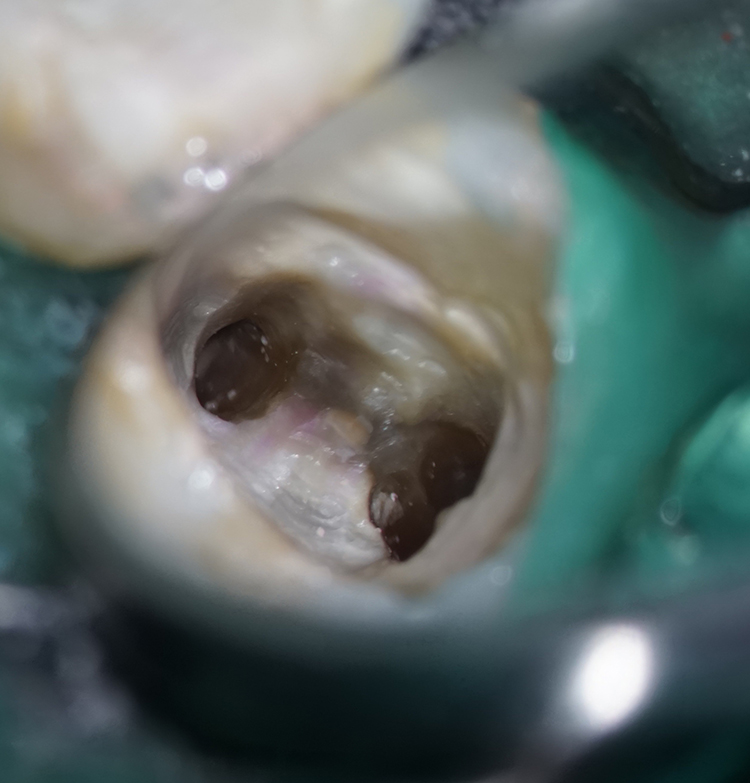

根管治療による根尖病巣の改善

根尖病巣の原因となっていた虫歯は銀歯に隠れて進行し、神経と歯の根を汚染していました。他医院で保険治療した銀歯を外しラバーダムと隔壁で治療中の感染防止をしたうえで、マイクロスコープによる拡大視野のもと丁寧に洗浄し、膿をだして根管を消毒しました。

自覚症状は出ていませんが、歯科用CT、デジタルレントゲンによる診断で隣の奥歯も根に感染の可能性がありました。これも同じように周囲の歯に感染を拡げないようラバーダムと隔壁で健康な歯を保護しながら進めます。